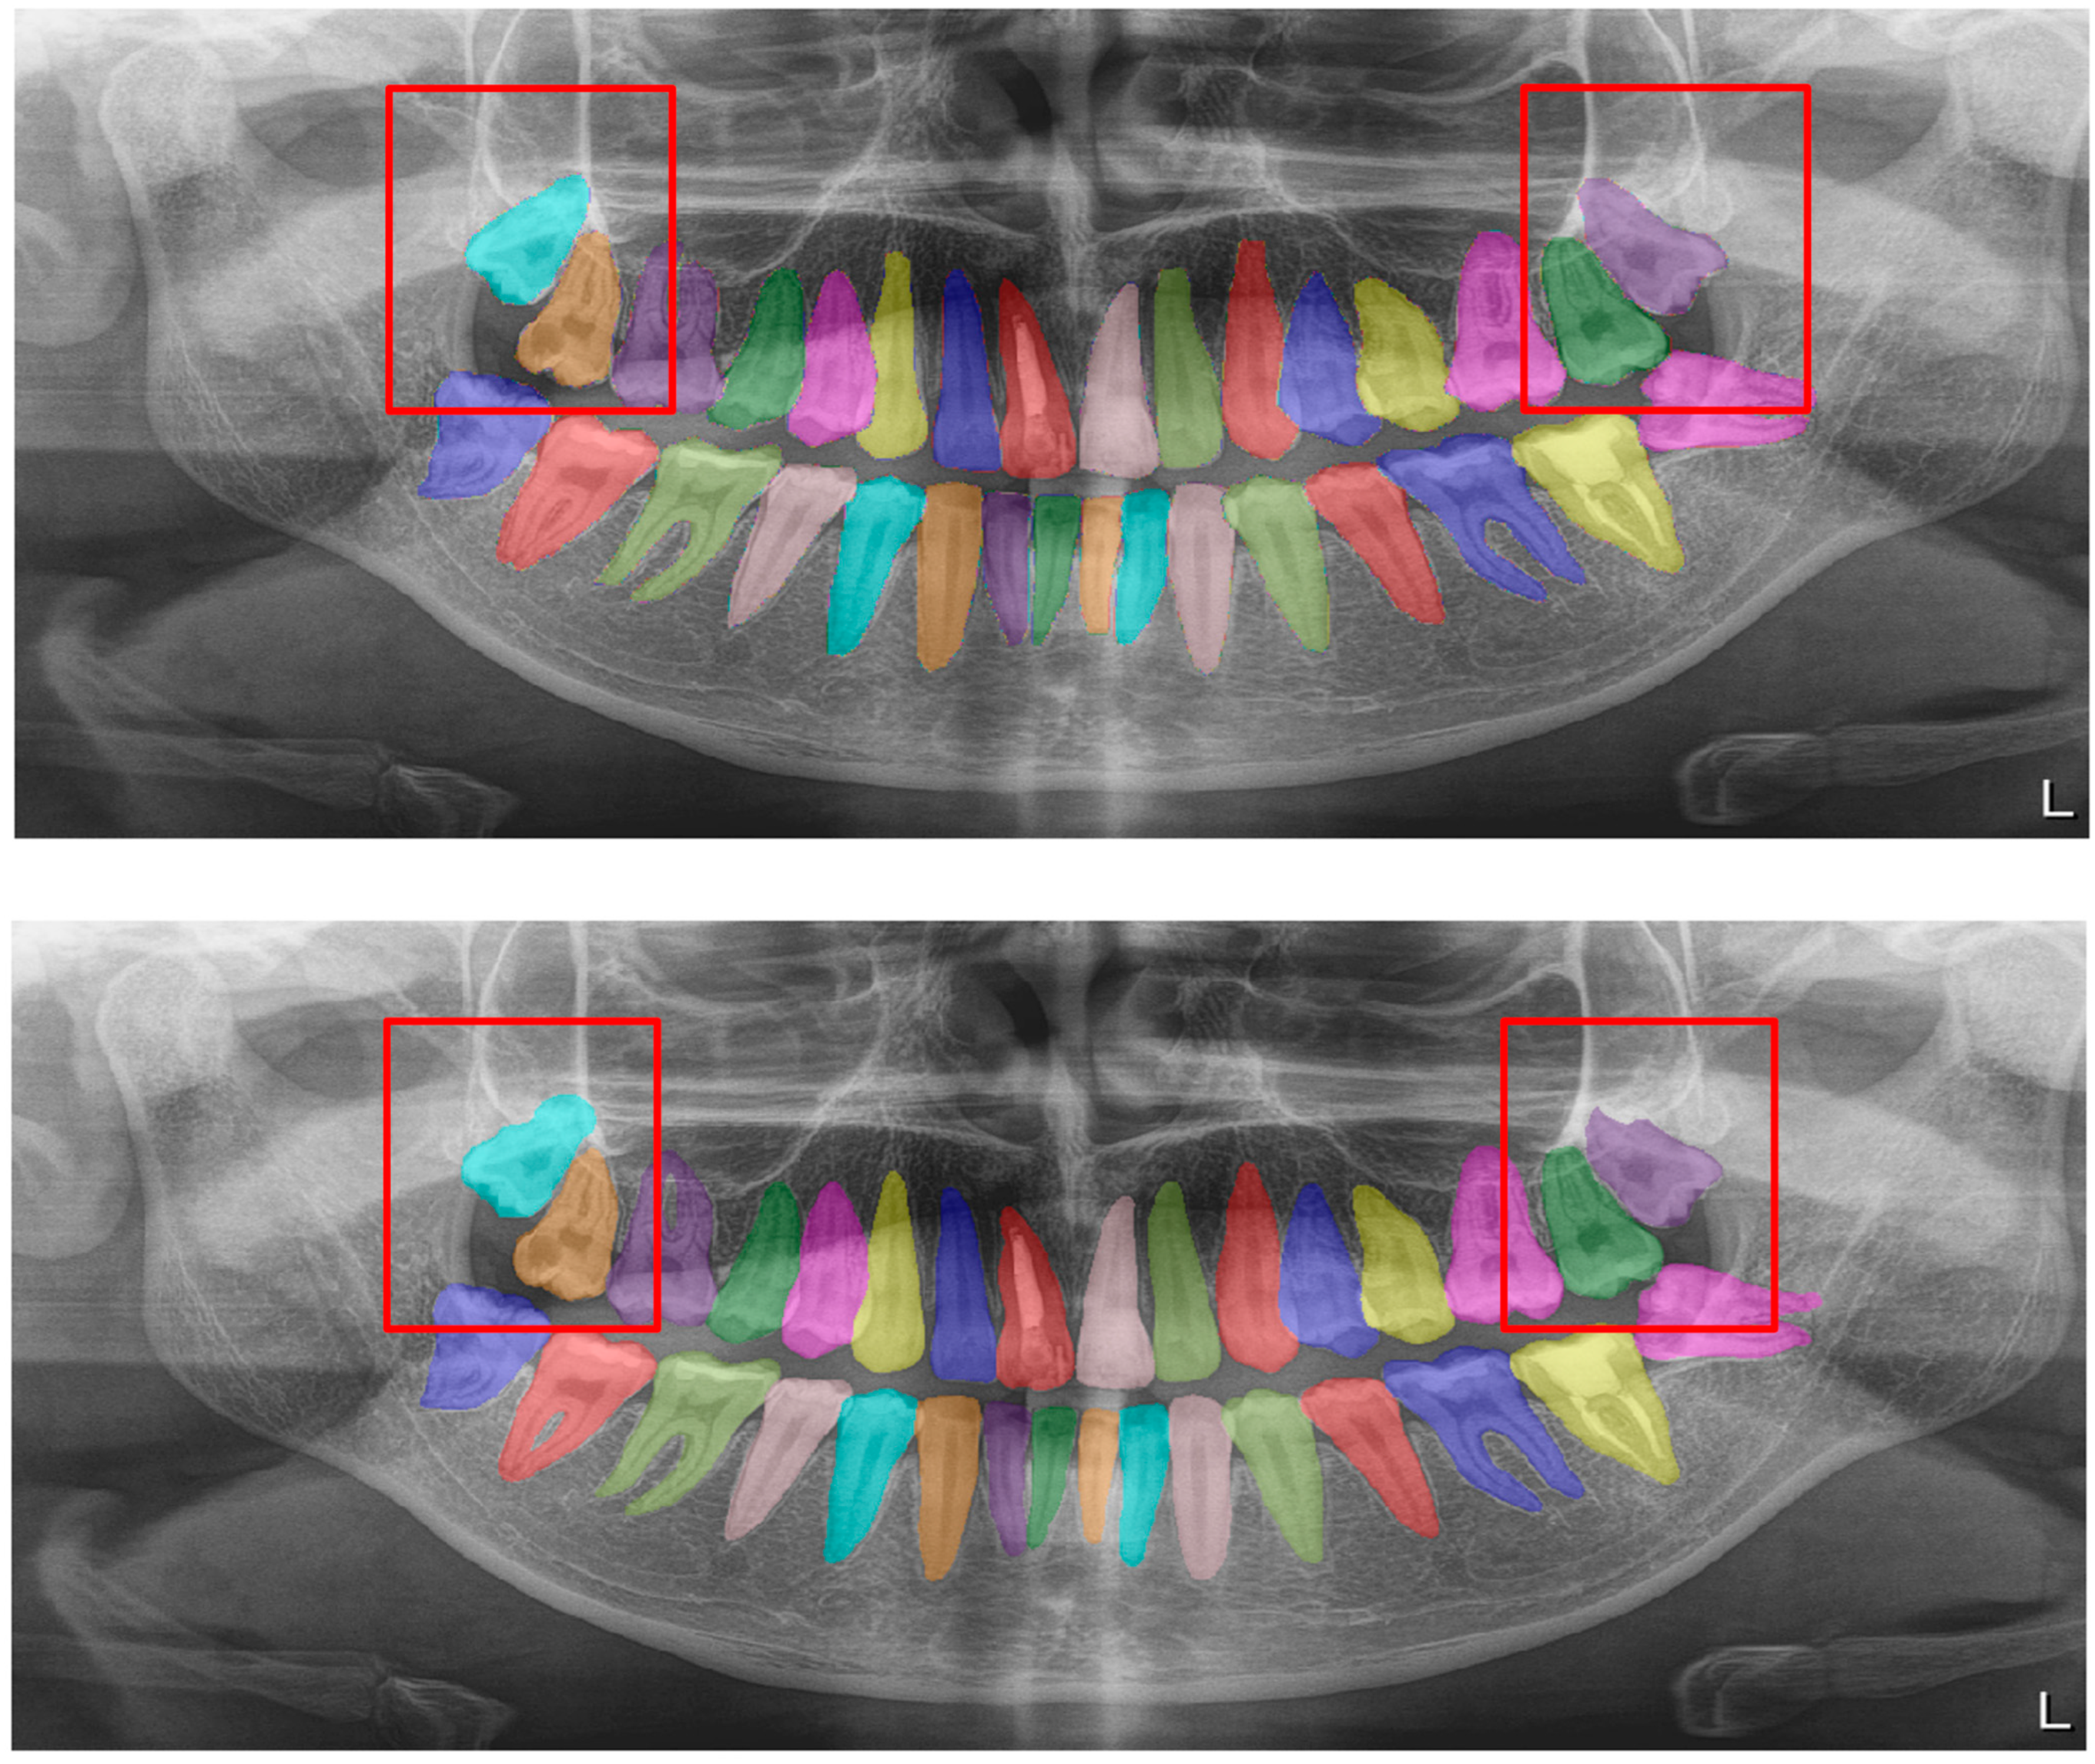

| Structure | DSC |

|---|---|

| Residual roots (Figure 7) | 0.78 |